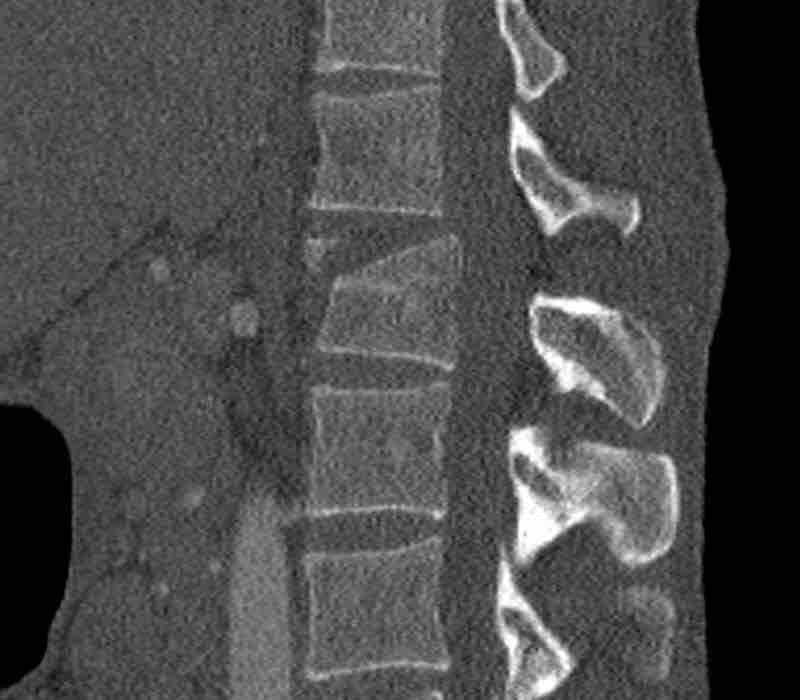

Scroll through images.

What is the highest AO-level?

Findings

- No dislocation ( no C type).

- Mainly horizontal fractures of spinous processus at multiple levels (B-type).

- Split fracture L2 (type A2).

Conclusion

Injury type B2 + A2 at level L2.